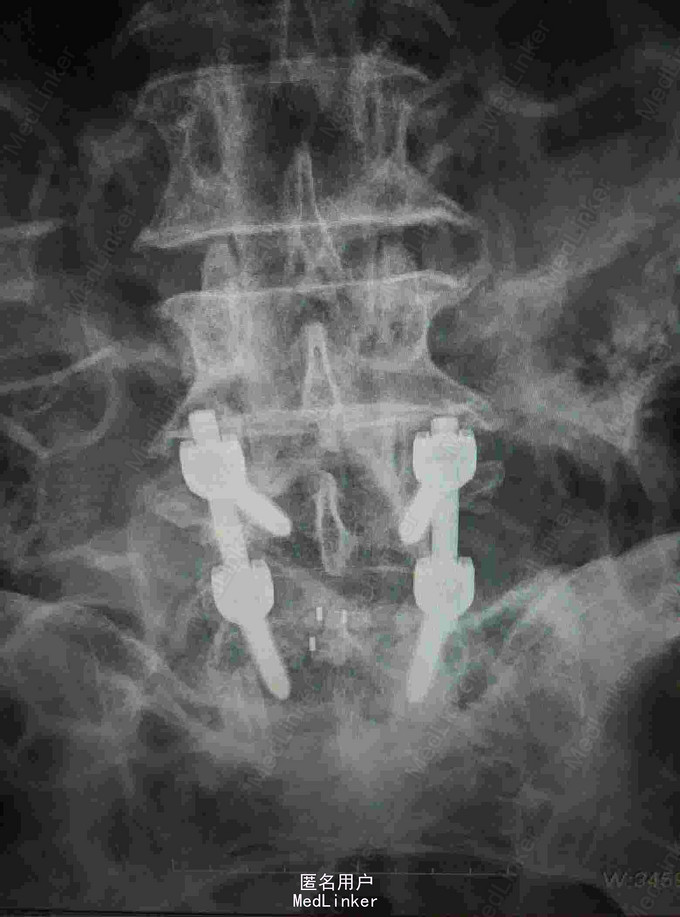

反复腰痛5年,加重伴跛行10余天 患者老年男性,5年前无明显诱因出现腰痛,休息后缓解,数年来反复发作,自行外用膏药对症治疗。近10余天来患者腰痛明显加重,伴跛行,右下肢疼痛,于当地医院就诊摄片提示腰椎退变,为进一步治疗入我院。

查体:腰4~5棘突及骶部压痛,无明显叩击痛,右大腿外侧疼痛,右足背外侧感觉减退,双下肢肌力正常,双侧直腿抬高实验阴性。 辅查:外院X线片提示腰椎退变 我院核磁提示腰4-5关节突增生内聚,椎间盘后突压迫硬膜囊及神经根

诊断:腰椎管狭窄 治疗:腰椎后路减压植骨内固定术